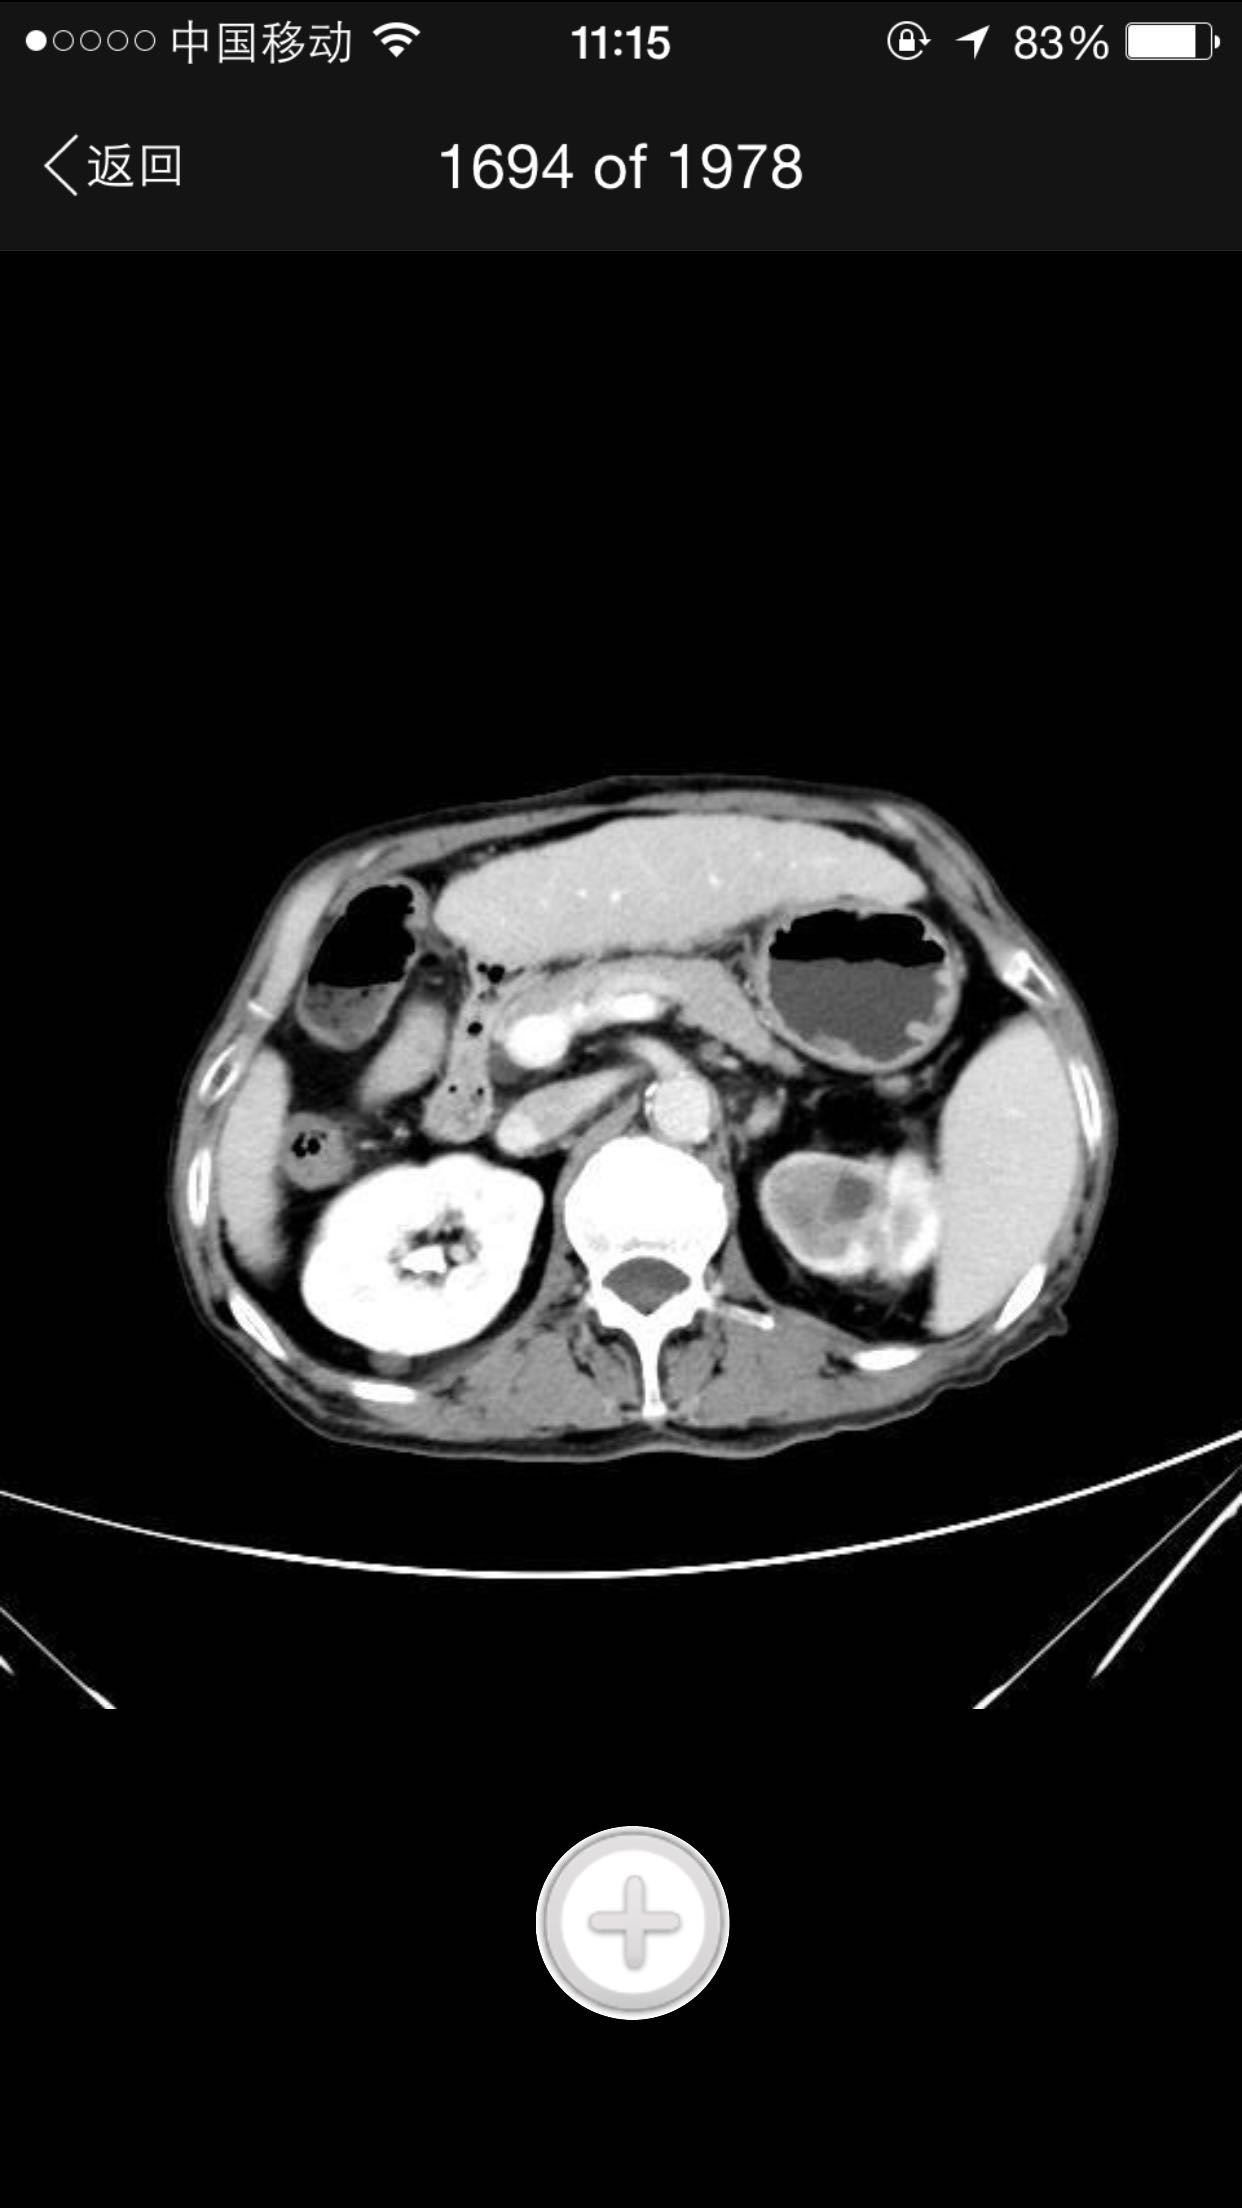

排尿困难,尿潴留入院。诊为前列腺增生症,拟行手术治疗。完善术前检查,泌尿系CT检查发现左肾占位,左肾结石并左肾重度积水,左肾萎缩等。既往患者肺结核病史,服药控制半年余。

查体:腹平软,无压痛及反跳痛,无肾区叩痛,肛诊前列腺明显增大,中央沟消失,无硬结,无压痛。术前强化CT提示左肾癌。

术前诊断:1、左肾癌2、左肾结石3、左肾积水4、左肾萎缩5、前列腺增生6、肺结核 入院后完善检查,拟行TURP,因发现左肾癌,改为先行肾手术。患者左肾癌,同时左肾结石,肾萎缩,决定行根治性肾切除,拟腹腔镜下手术,患者家属不同意,改开放手术,全麻下行根治性左肾切除。术后剖开标本如下图,肿瘤位于肾上极,中间黑色为结石。